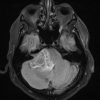

U dây VIII

» Thông tin: Nam giới – 50 tuổi.

» Lâm sàng: Đau đầu + Mất thính giác phải.